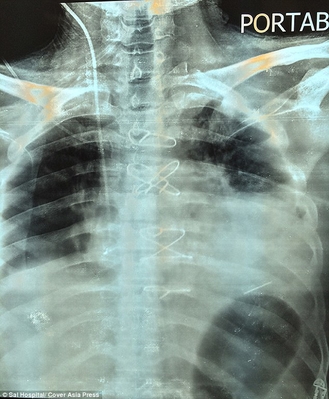

Доктор Анил Джейн, кардиохирург, который руководил операцией, сказал, что это был очень редкий случай, и удивительно, что пациент жил с пулей в сердце в течение двух месяцев: "Пуля находилась в сердечной мышце у верхушки левого желудочка, одной из двух камер сердца. Это уникальный случай, который запросто мог стать фатальным. То, что он прожил два месяца с пулей в таком месте - уникальный случай, это очень счастливый человек"

Во время трехчасовой операции команде из пяти врачей пришлось остановить сердце пациента и поддерживать его с помощью аппарата искусственного кровообращения. Только так они могли извлечь пулю. Оперативное вмешательство прошло успешно и сейчас Бхарат Шарма восстанавливается в отделении интенсивной терапии больницы. Пулю, которая в любой момент могла его убить, он хочет сохранить в качестве напоминания о том, как близко он подошел к смерти.